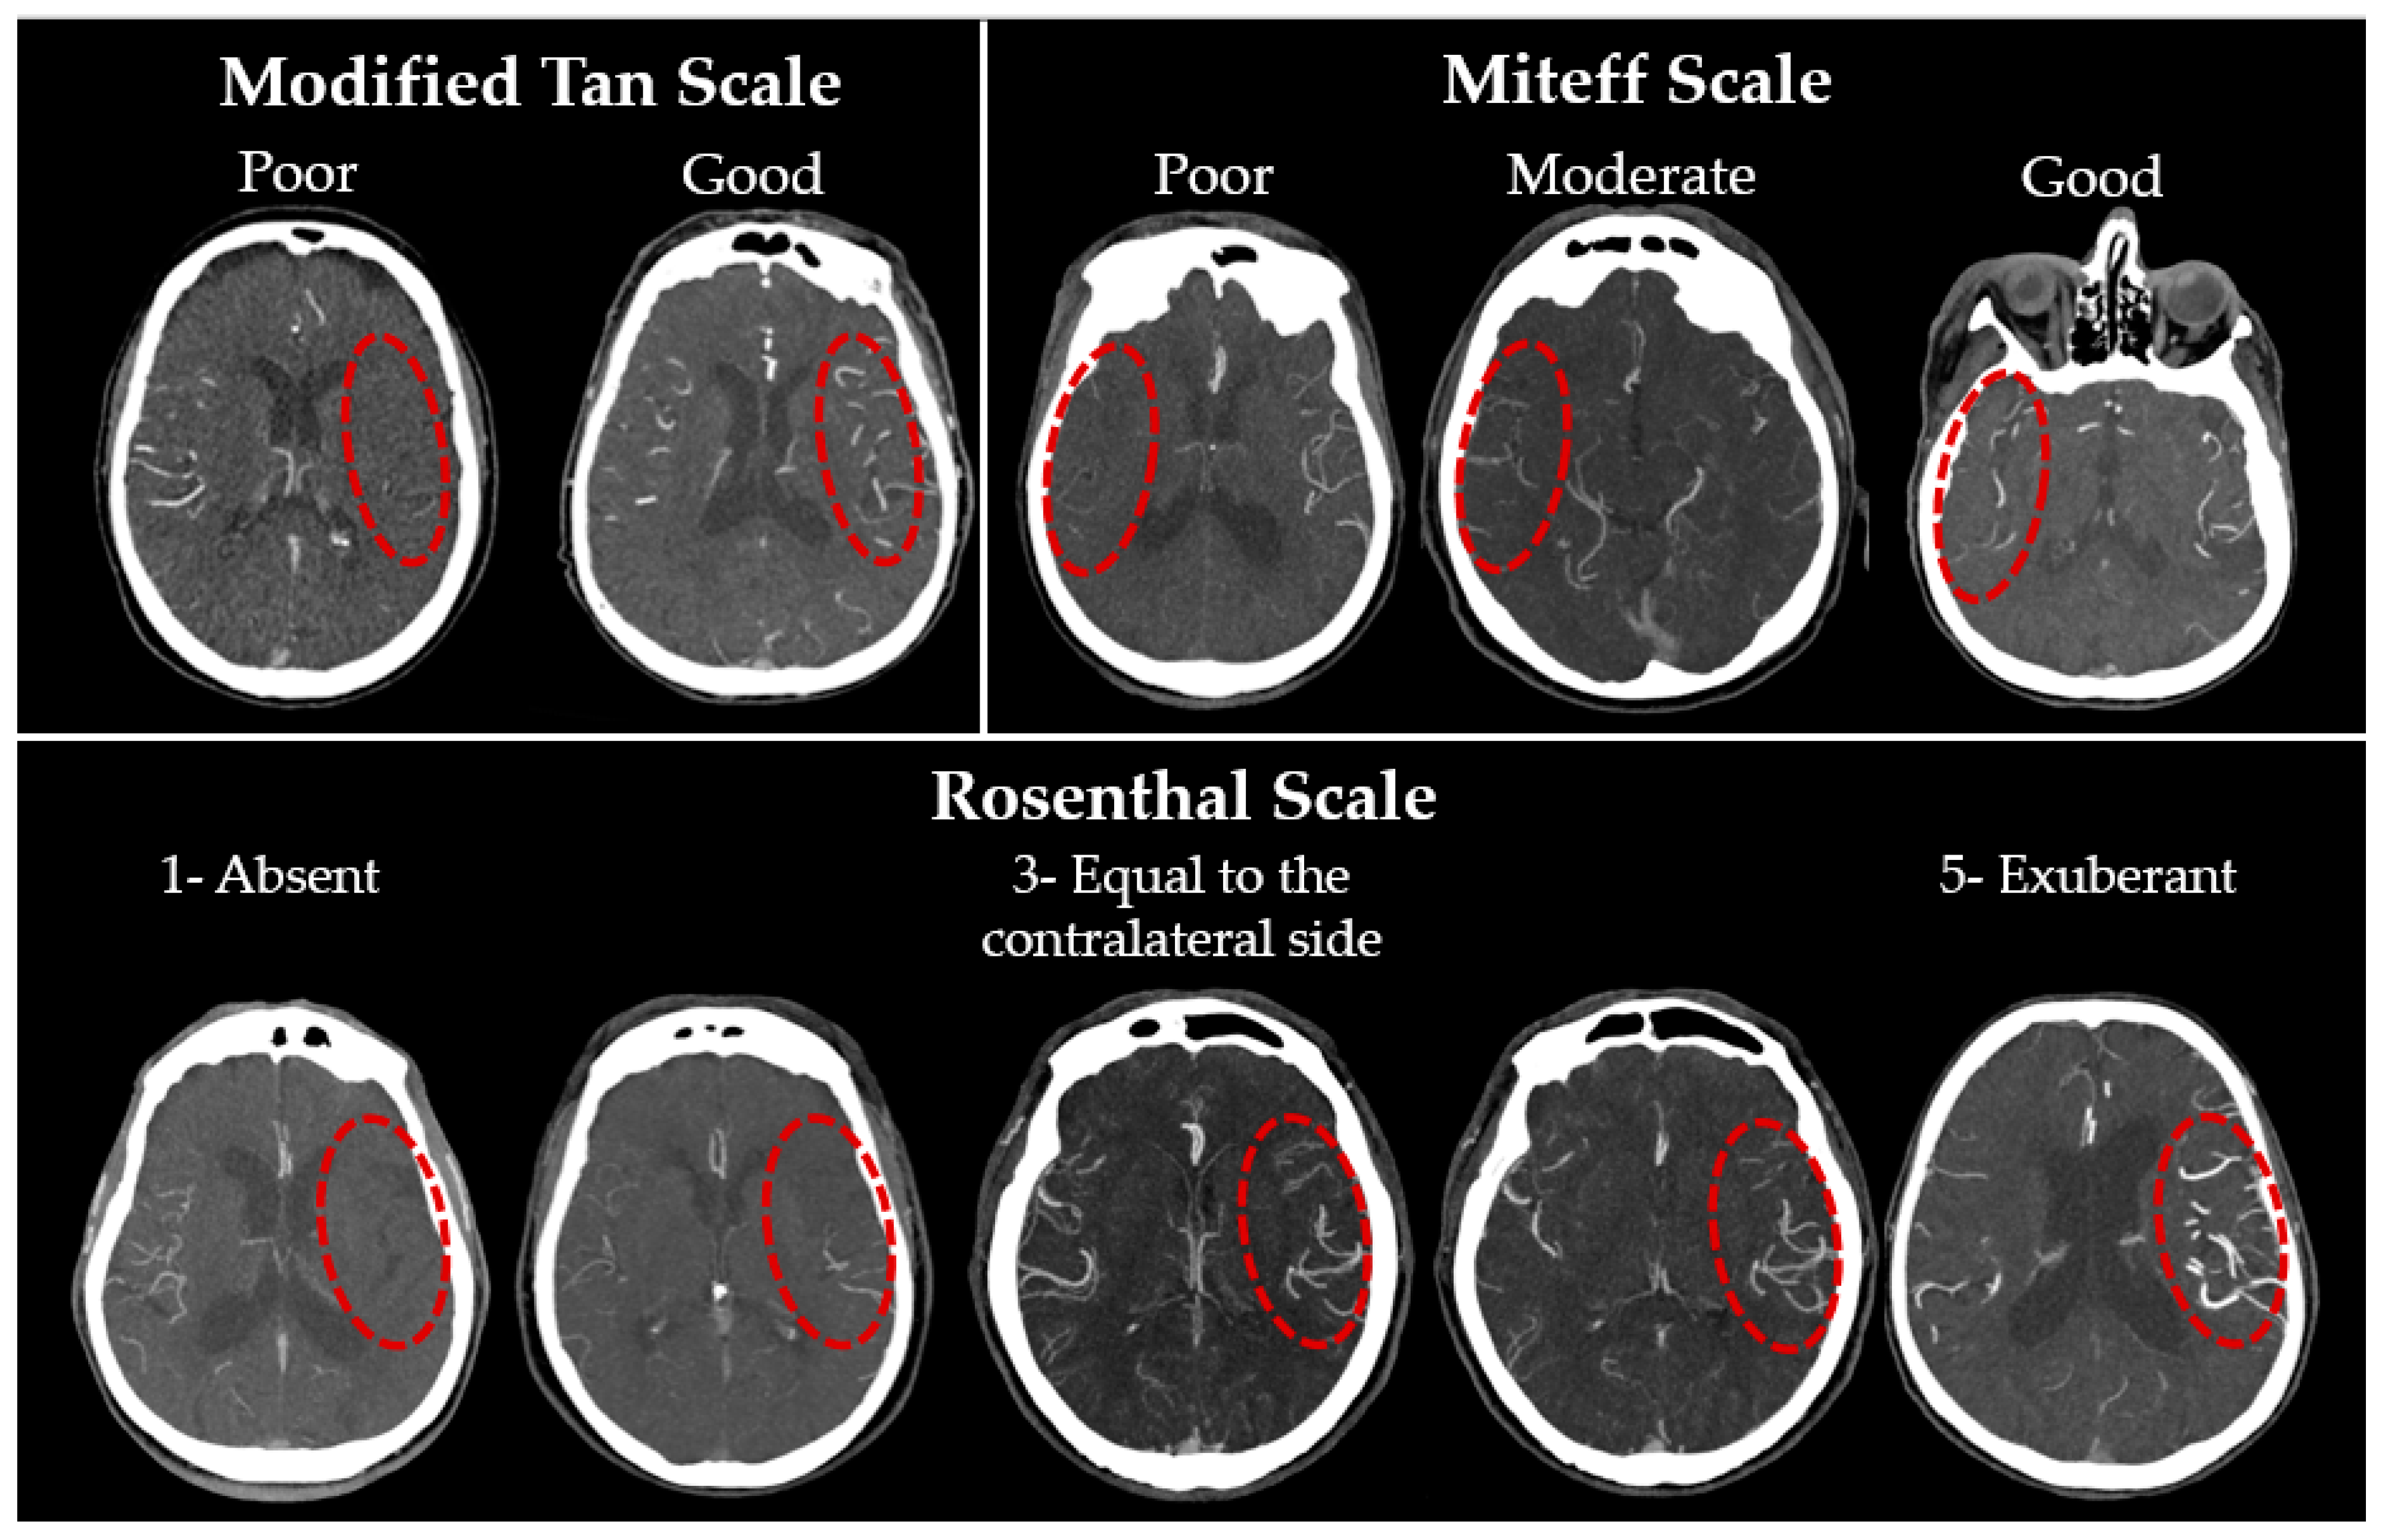

- The modified Tan scale [25] is based on the binary classification proposed in 2002 by Shramm et al. [21]. This classification is both the simplest and, according to the published works, one of the most reliable [38,39], probably due to the minimal number of grades. A ‘good’ grade is given if collaterals are seen on more than 50% of the MCA basin.

- The Miteff scale [20]: the authors propose characterising CS on the basis of the maximum-intensity projection (MIP) according to the following three grades: poor collaterals—only distal superficial branches of the MCA are visible; moderate collaterals—in addition to superficial arteries, the branches of the MCA in the Sylvian sulcus are also visualised; good collaterals—MCA is visualised immediately after the occlusion site. Previously, this system also demonstrated a high inter-rater reliability [39].

- The Rosenthal scale [27]: unlike the previous two, this classification is based on the comparison of the affected side with the intact one and includes five gradations: (1) absent vessels; (2) vessels are less than on the contralateral normal side; (3) vessels are represented to the same extent as on the intact side; (4) vessels are greater than on the contralateral normal side; (5) exuberant vessels on the affected side. The authors originally proposed using only CTA-SI, but as MIP and MPR are now firmly integrated into any workstation routine, they were also assessed. Examples of gradations for each scale are presented in Figure 1.